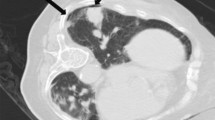

Middle lobe, lingular, and lower lobe lesions were categorized as “lower locations”; upper lobe lesions, as “upper locations” [11]. Lesion size was measured as the largest diameter of the sampled lesion in the previous CT images. The depth of the lesion was gauged as the length of the needle track from the punctured pleura to the edge of the lesion sampled. The needle-pleural angle was calculated on the transverse 3-mm section in the craniocaudal dimension, according to the method suggested by Ko et al. [6]. It was defined as the minimum angle formed by a line tangent to the pleura at the puncture point and a line drawn along the needle (Fig. 1) [6]. Pneumothorax was evaluated by CT scan after biopsy, as the largest separation between the visceral and parietal pleura. Less than or equal to 1 cm was categorized as “minor pneumothorax”; greater than 1 cm but less than or equal to 2 cm, as “intermediate pneumothorax”; greater than 2 cm, symptomatic or chest drainage catheter insertion needed, as “severe pneumothorax” [12].

a CT-guided core needle biopsy of a solitary suspected lesion in the right lower lobe, in a 56-year-old male patient with 6 pack-years smoking. b Showed the biopsy needle (arrow) inserted within the lesion, which was later pathologically confirmed to be pulmonary adenocarcinoma. The patient was in lateral position on the CT table. The needle-pleural angle (curved white arrow), which was the minimum angle formed by a line tangent to the pleura at the puncture point and a line drawn along the needle, was 63°. The length of the needle track from the pleura to the lesion was 14.4 mm. The dwell time was 660 s. c CT image after the removal of the biopsy needle showed pneumothorax (arrowhead), which continued to increase until the chest drainage catheter was inserted

PCNBs were performed by one intervention team led by Prof. C. L. (7 years of experience in CT-guided needle biopsy), using only one type of needle, 17-gauge coaxial introducer and 18-gauge automated cutting needle (Biopince, Argon Medical Devices, Frisco, Texas). All the biopsies were carried out according to the standard protocol. All patients underwent enhanced CT before the biopsy. Averting obvious emphysema or bulla, the safest and shortest route from the chest wall to solid part of the lesion was chosen to determine the supine, prone or lateral position of the patient on the CT table. All patients were given intravenous indwelling needles, allowing for the infusion of rescue drugs if necessary. The patients were instructed to breathe shallowly and avoid moving, coughing, speaking or deep breathing during and 3 h after the procedure. If the biopsy route needed to be changed, the patient's position could also be changed. After aseptic technique and local anesthesia with 1% lidocaine, the introducer needle was inserted. The needle is inserted rapidly during pleural puncture, and the needle is withdrawn slowly after the biopsy. Rapid insertion at breath-hold can form a precise puncture point, while slow extraction of the guide needle can make the elastic lung tissue seal the pleural hole. Then the position of the coaxial introducer was determined by CT scan. If the introducer was correctly located within the periphery of the lesion, the biopsy was performed to obtain sufficient tissue samples. The representative images of the CT-guided PCNB are shown in Fig. 1. After slowly removing the needle, CT scan was performed to evaluate the complications. The patient was then asked to rest for 24 h. Patients with pneumothorax or bleeding were monitored in the inpatient ward. Patients with intermediate or severe pneumothorax were arranged to have a follow-up CT scan to determine its stability. If patients had pneumothorax with symptoms of respiratory distress or shortness of breath, a closed thoracic drainage (8 Fr. pig-tail) was performed.